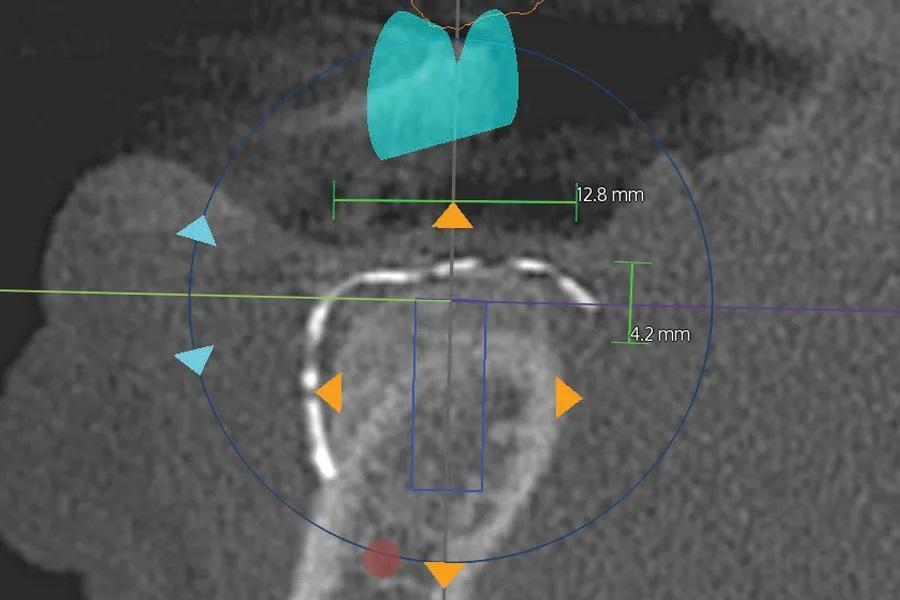

Послеоперационный период прошел без осложнений. КЛКТ, выполненная через 6 месяцев, показала формирование зрелой костной ткани под сеткой в запланированных местах установки имплантатов (Фото 5–7).

Фото 6. Корональный срез КЛКТ в области запланированного имплантата второго премоляра правой нижней челюсти (вертикальный синий прямоугольник в центре изображения). Зеленые линии и соответствующие числа указывают вертикальные и горизонтальные измерения аугментированной кости: 4,2 мм и 12,8 мм соответственно.